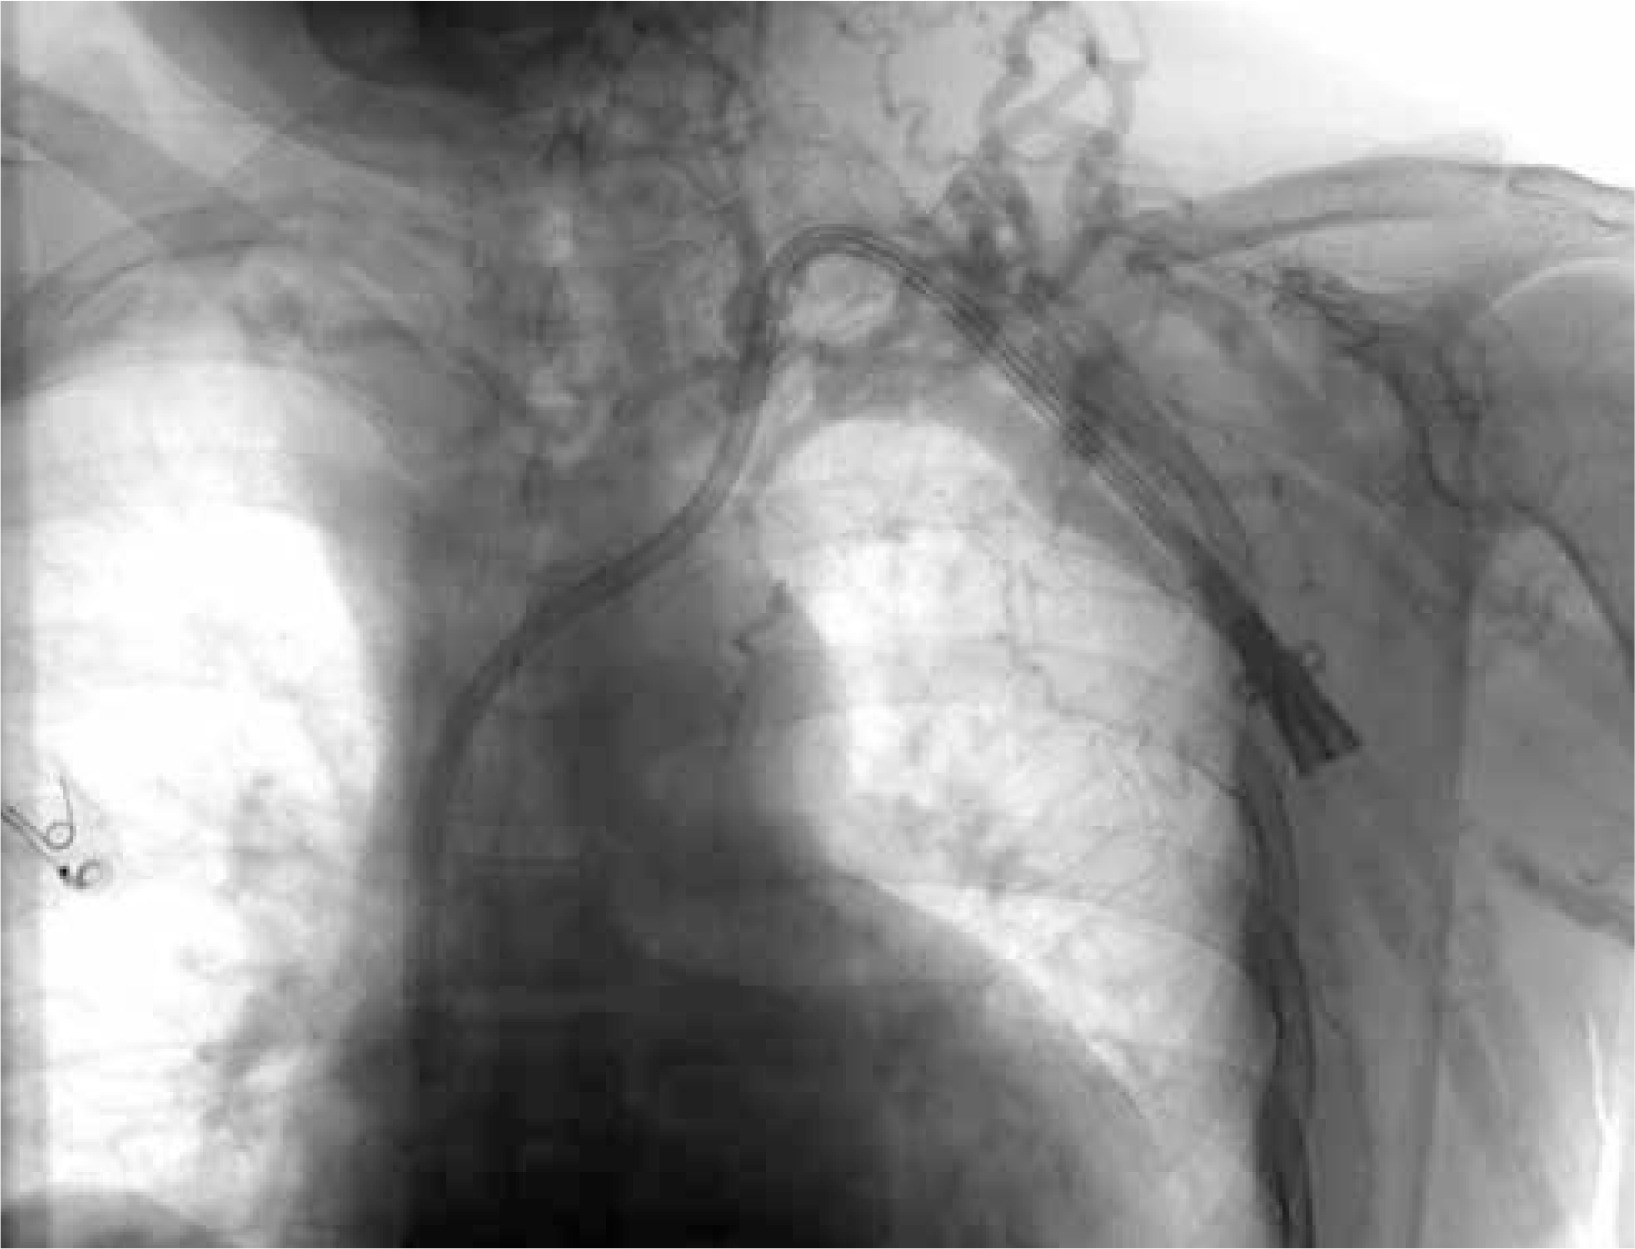

The patient’s upper extremity Doppler and left upper extremity venography, conducted at an external center, revealed total occlusion (Figure 1). Due to the impassable lesion resulting from complete blockage, only diagnostic imaging could be performed. Subsequently, hospitalization was deemed necessary for further investigation and treatment. Venous phase upper extremity computed tomography angiography revealed the condition. The right subclavian vein was identified as patent, prompting the decision to plan a subclavian venous cross-over bypass from left to right. Following preoperative preparations for the patient, the surgical procedure was initiated.